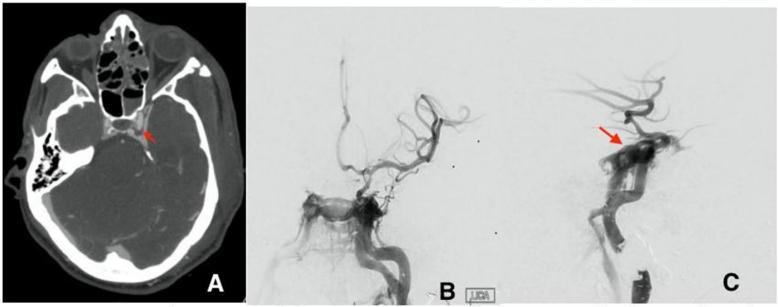

头颈部CTA显示颈动脉管左侧颅内ICA轻度不规则。在术后3天内,重复进行头部和颈部CTA检查,发现左侧颈内动脉海绵状段有一个新的4mm假性动脉瘤(图2A)。常规脑血管造影显示左侧tCCF存在高流量,血管造影证据显示颅内血流受损(图2B,C)。考虑了球囊闭塞试验(BTO)。然而,球囊扩张前血压下降与左脑体感电位的丧失有关。随后中止BTO并优化血压以确保左脑的适当灌注。

图2. (A)左侧海绵状假性动脉瘤的初始CTA(红色箭头)。(B)第一次脑血管造影AP视图和侧视图(C)显示了破裂假性动脉瘤部位左侧ICA海绵窦段和左侧海绵窦之间的直接瘘管